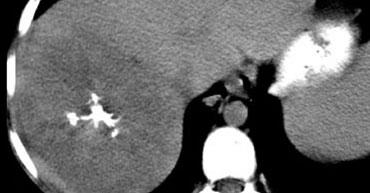

U máu khổng lồ có mô sẹo. Lưu ý mức độ ngấm thuốc tương đương hồ máu ở tất cả các thì. Sẹo trung tâm giảm tỷ trọng trên NECT và vẫn giảm tỷ trọng ở các thì sau.